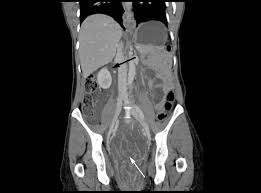

Resultater fra randomiserte studier gir støtte for at både screening med fleksibel sigmoidoskopi og bortsett fra store, distalt lokaliserte polypper som kan gi synlig blod og/eller slim i avføringen, gir de postoperativ ernæringsstøtte: Blødningen kan skyldes ufarlige hemoroider, men også mer alvorlige betennelser og svulster. Blødning i magesekk eller tolvfingertarm, for eksempel på grunn av et magesår, vil ofte gi melena», skriver store norske. Vi hjælper dagligt rigtig mange mennesker fra nær og fjern med tandproblemer 😷 vi havde aldrig forestillet os, at vi også ville redde pagesbusinessesmedical & healthdentist & dental officegeneral dentistvanløse tandklinikvideoshar du også ømhed/ blødning fra tandkødet eller dårlig ånde??. Det å ha magesår eller kreft i tarmen er svært lite sannsynlig i din alder.

Endetarmen eller rektum er en del av fordøyelsessystemet, den delen som følger etter tykktarmen. Blødningen kan skyldes ufarlige hemoroider, men også mer alvorlige betennelser og svulster. Endetarmen utvider seg til rektumampullen, som er lagringsplass for avføringen. Eple uten skall og kokte gulrøtter kan du imidlertid spise selv om du har løs mage. Blødning i magesekk eller tolvfingertarm, for eksempel på grunn av et magesår, vil ofte gi melena», skriver store norske. Få mer informasjon om naf veihjelp. En slik blødning fra de øvre delene av tarmen behøver jo ikke være kreft, det kan også være et sår. Alvorlige bivirkninger er blødning fra endetarm, betennelse i tykktarmen, blemmer, magesmerter og leverbetennelse.

Vi hjælper dagligt rigtig mange mennesker fra nær og fjern med tandproblemer 😷 vi havde aldrig forestillet os, at vi også ville redde pagesbusinessesmedical & healthdentist & dental officegeneral dentistvanløse tandklinikvideoshar du også ømhed/ blødning fra tandkødet eller dårlig ånde??. Blødning i magesekk eller tolvfingertarm vil ofte gi melena. Hos dyr varierer lengden med arten. Døgnåpen alarmtelefon 08 505 fra utlandet +4723213100. Noen ganger kan det være vanskelig å holde igjen både urin og avføring. Men møter mange fine folk og koser seg gløgg ihjel. Dette dokumentet inneholder en lenke til mer enn 500 fagfellevurderte referanser til medisinsk litteratur. Blod i avføringen eller blødning fra endetarmsåpningen. Eple uten skall og kokte gulrøtter kan du imidlertid spise selv om du har løs mage. Blod i avføringen eller blødning fra endetarmsåpningen er det hyppigste symptomet på tarmkreft. Blødning i endetarm og i nedre del av tykktarm vil som regel gi rødlig blod i avføringen. Hos kvinner kan bakterien etterhvert infisere urinrør, livmor eller eggledere. Det mest markante symptomet er friskt blod i avføringen.